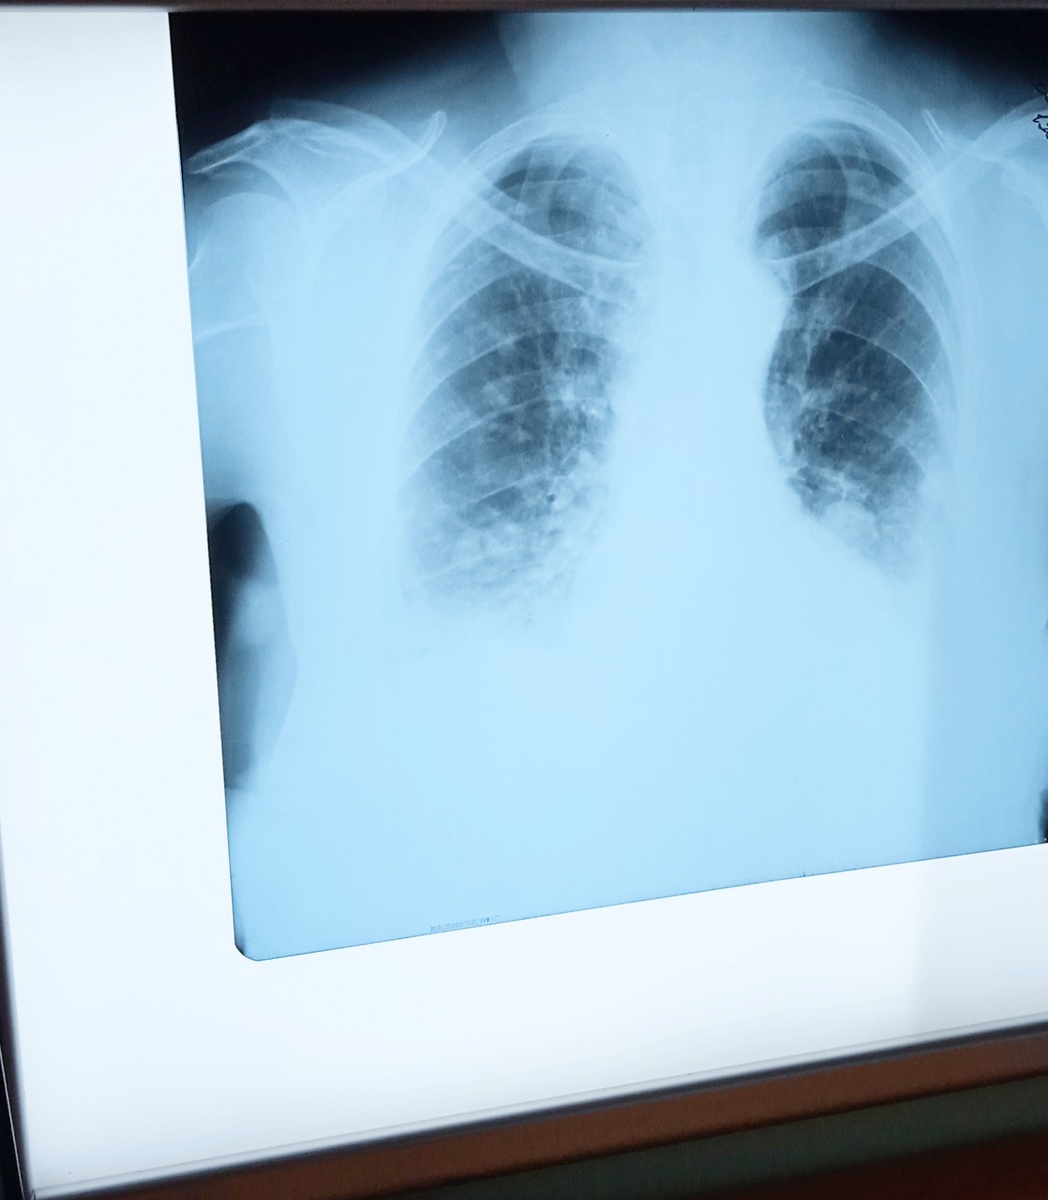

В питерской школе детей кормил больной туберкулёзом сотрудник кухни

В школе №575 Санкт-Петербурга сотрудник буфета, уже будучи больным, приступил к работе. Когда факт заболевания стал достоянием общественности, администрация школы выбрала тактику замалчивания. Учеников 9-11 классов экстренно отправили на флюорографию, а детям с 1 по 8 класс провели диаскинтест. Об этом в своём обращении к Мизулиной рассказали дети и сотрудники. При этом официальные результаты проверок скрываются, карантин не введён, а педагогам под угрозой дисциплинарного взыскания запретили обсуждать произошедшее.

По официальным данным, заболевший сотрудник госпитализирован и проходит лечение. Помещения продезинфицированы, а медосмотр прошли почти все учащиеся. Повторных случаев заражения не выявлено. Роспотребнадзор заявляет, что ситуация под контролем и оснований для карантина нет. В ближайшее время для родителей обещают провести собрания с медиками, чтобы разъяснить реальные риски.

Похожая история произошла в гимназии №3 города Южно-Сахалинск. Здесь у одного из сотрудников выявлена открытая, то есть заразная, форма туберкулёза. Несмотря на это, учебное заведение продолжает работать в штатном режиме, карантин до сих пор не объявлен. Этот случай также стал известен Мизулиной, она об этом написала в своём телеграм-канале.